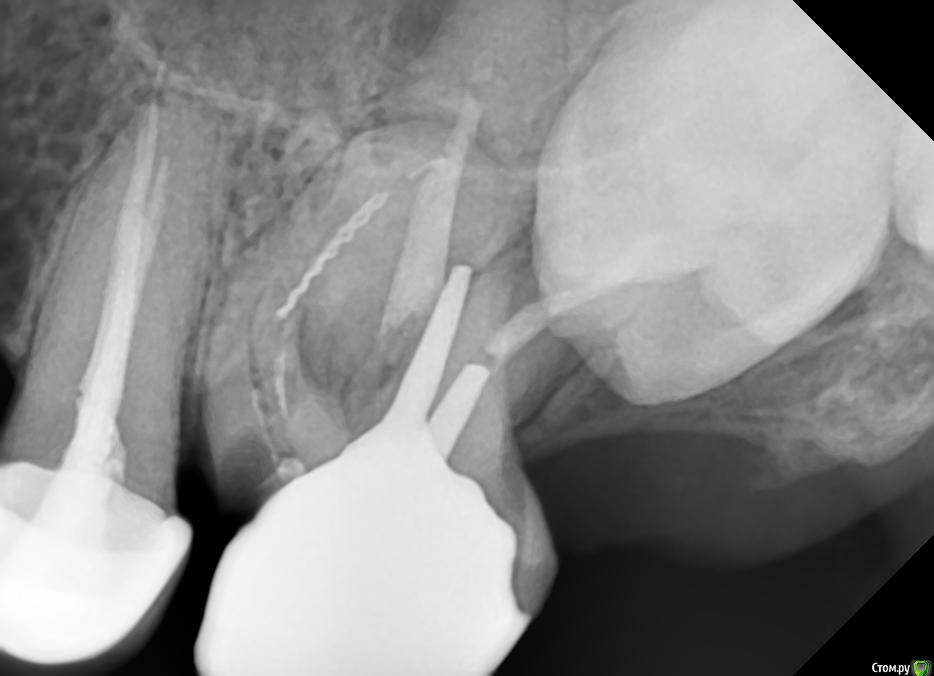

alex_chaikin_88 Опубликовано 1 августа, 2018 Поделиться Опубликовано 1 августа, 2018 Добрый день! Подскажите, 5 лет назад сделал зуб. Проблем не было. Сейчас заболел. Сделал снммок, доктор сказала, что нужно удалять. Тпа там поломанный инструмент оставили и вообще он не доделан. Приложу снимок. Просто дайте комментарий. Спасибо. P.s. зуб цел внешне, и удалять не хочу. Мне кажется там зуб мудрости пытается вылезти через этот зуб. Извините если не в ту тему написал Ссылка на комментарий

chervoncevdaniil Опубликовано 1 августа, 2018 Поделиться Опубликовано 1 августа, 2018 Там серьезно оставили инструмент?Его там не оставляли,он сломался за изгибом корня,такое к сожалению случается.Зуб удалять не по причине сломанного инструмента,это решается,а по причине кариеса под пломбой,который сейчас ушел очень глубоко под десну и восстановить такой зуб не представится возможным 1 Ссылка на комментарий

Jurai Опубликовано 1 августа, 2018 Поделиться Опубликовано 1 августа, 2018 Панорамного снимка, случайно, нет? Это, как мне показалось, не восьмерка лежит. Удалять зуб не столько из-за инструмента, а из-за кариеса корня. Внешне зуб целым выглядит, похоже, из-за коронки. Ссылка на комментарий